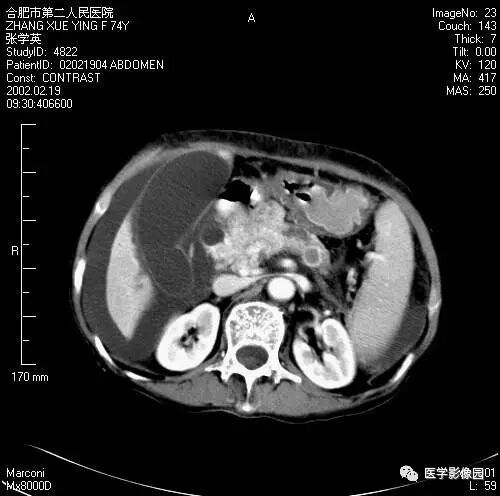

图6-4-9胰腺癌

A.CT平扫见胰头等密度肿块,

钩突明显圆隆;

B.增强扫描动脉期钩突内见境界

不清低密度灶(↑);

C.胰头部可见扩张的胆总管(↑)和

主胰管(长↑),即双管征